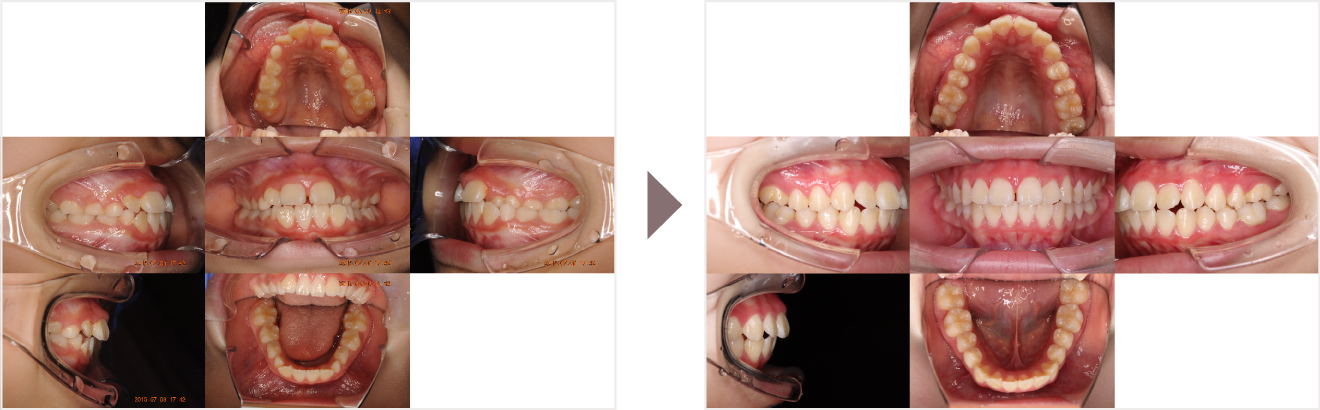

症例叢生

性別

期間6年10ヶ月

治療内容N-Bimler装置、Neo-Capを使用して治療

治療における

副作用・リスク

装着しないと効果は出ません

金額ビムラー装置:550,000円

ネオキャップ:8本

合計:594,000円